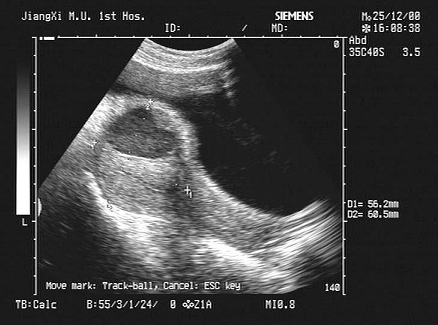

[单选题]女性,44岁,取环术后下腹疼痛1天。B超检查如图,最可能的诊断为()A . 子宫血肿B . 盆腔血肿C . 子宫肌瘤D . 子宫腺肌瘤E . 肌瘤囊变